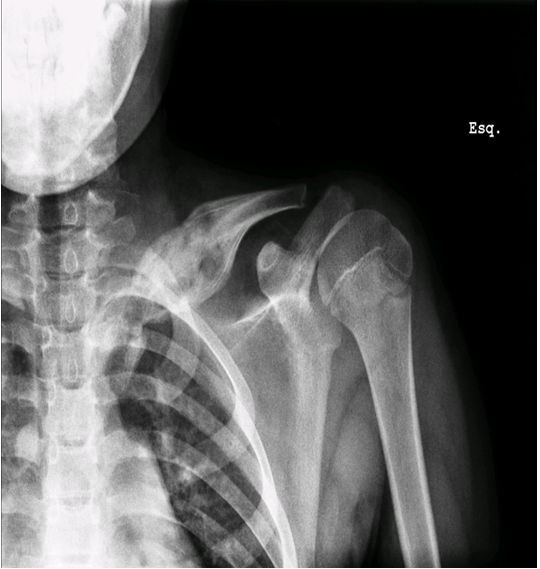

This is a case of an 11-year-old boy with left clavicle pain with two months of evolution presented to emergency department. No history of trauma, fever or systemic signs, recent illness and no relevant personal or familiar medical history. No neurological or vascular abnormalities were found in the upper arms. Left shoulder X-ray revealed a hyperdense lesion and increased thickness of left clavicle (Figure 1). In this context a computed tomography (CT) scan and after a magnetic resonance imaging (MRI) scan were ordered. Both scans demonstrated morphological changes of the median half of the clavicle, cortical destruction and periosteal reaction. Also changes in the surrounding soft and muscular tissue and bulky and numerous locoregional ganglion formations (Figure 2) and (Figure 3). Blood analysis, blood cultures and bone biopsy were negative for infection and neoplastic disorder. In this context, by exclusion, and in the presence of two Jansson major diagnostic criteria (radiologically proven osteolytic/osteosclerotic bone lesions and sterile bone biopsy with signs of inflammation) [1], we reached the diagnosis of chronic recurrent multifocal osteomyelitis (CMRO) (Table 1). Patient was treated with NSAIDs for six months and a short course of corticoids without any response. By keeping complaints of marked and recalcitrant pain in clavicle region, we opted for the surgical treatment: resection of the lesion en bloc, about 7 cm of clavicle (Figure 4), maintaining the integrity of periosteum to allow neo-osteogenesis of the clavicle. No bone grafting or another material was interposed in the dead space left by the resection of the clavicle. Post operatory X-ray, showing a radiopaque area corresponding to the excision of the medial portion of the clavicle (Figure 5).

Figure 1: X-ray revealed a hyperdense lesion and increased thickness of left clavicle.